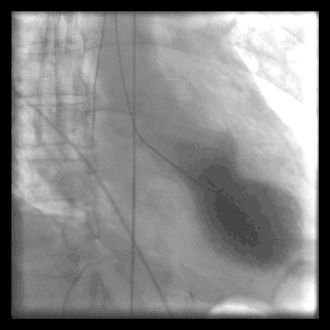

![]() Left ventriculography during systole showing apical ballooning akinesis with basal hyperkinesis in a patient with takotsubo cardiomyopathy. | |

Cardiac ventriculography is a medical imaging test used to determine a person's heart function in the right, or left ventricle.[1] Cardiac ventriculography involves injecting contrast media into the heart's ventricle(s) to measure the volume of blood pumped. Cardiac ventriculography can be performed with a radionuclide in radionuclide ventriculography or with an iodine-based contrast in cardiac chamber catheterization.